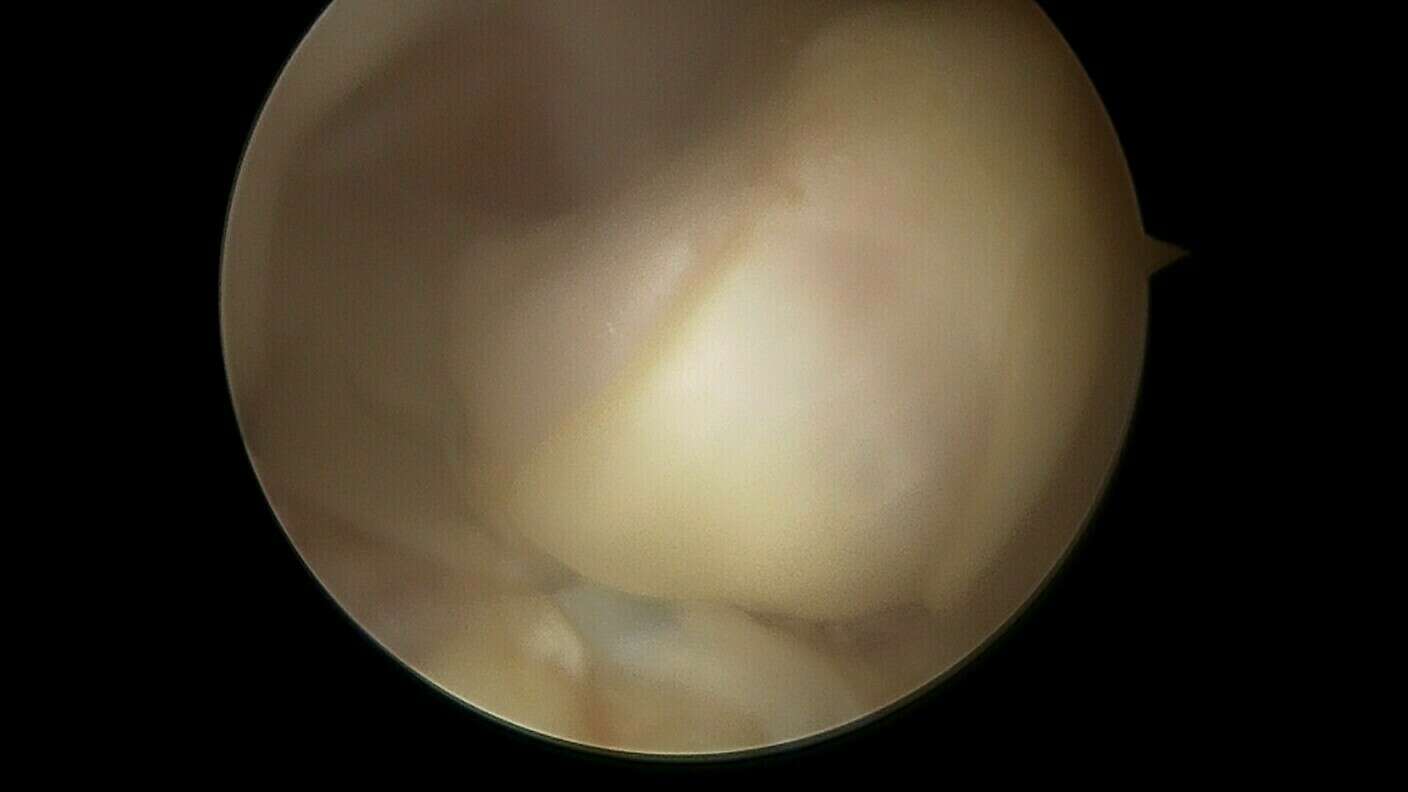

Le diagnostic de cette lésion se fait par la recherche de signes cliniques évocateurs et par l’IRM qui retrouve généralement un nodule à la face antérieure de la plastie ligamentaire au niveau de l’échancrure inter-condylienne sur lequel vient buter la trochlée fémorale.

En l’absence d’évolution spontanément favorable, le traitement est systématiquement chirurgical et consiste à retirer ce nodule d’arthro-fibrose sous arthroscopie au cours d’une hospitalisation de courte durée en Chirurgie Ambulatoire. Lors de l’intervention chirurgicale, le chirurgien s’assurera de la récupération de l’extension complète du genou.

Galerie photo